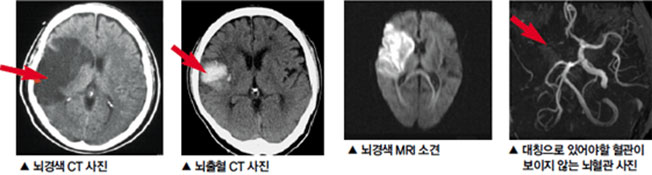

뇌혈관이 막히거나 터지는 질환을 부르는게 뇌졸중이고 그 중 뇌혈관이 막히는게 뇌경색 그리고 뇌혈관이 터지는 것을 뇌출혈이라고 합니다. 뇌졸중은 영구적인 손상이 많다고 하며 증상에 따라 전신이나 육체 일부 기능이 마비되는 등의 극심한 후유증이 남는 무서운 질병입니다 오늘은 뇌경색 초기증상에 대하여 알려드리도록 하겠습니다.

허혈성 뇌졸중은 발생 기전에 따라 대혈관 질환에 의한 뇌경색, 심인성 뇌경색 또는 심인성 뇌경색, 소혈관 질환 또는 틈새 뇌경색, 기타 드문 이유가 되는 것에 의한 뇌경색으로 나누어져요. 에피소드는 일정 기간 동안 증상이 완전히 가라앉는 경우입니다.

허혈성 뇌졸중의 대표적인 이유가 되는 것은 고혈압, 당뇨병, 고지혈증 등으로 인해서 뇌에 혈액을 전달하는 혈관에 동맥경화(동맥경화)가 발생하여 뇌로 가는 혈류를 차단하는 것입니다.